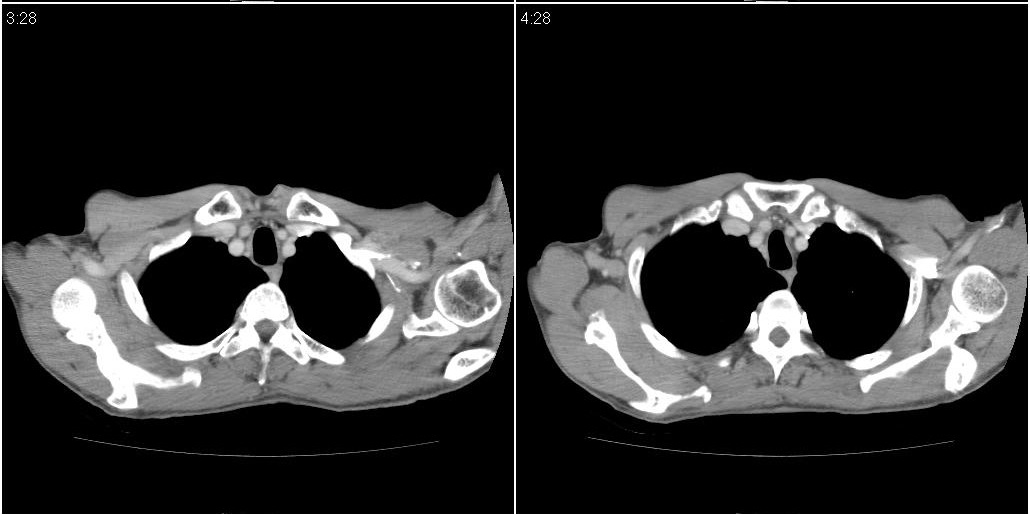

以下是ct检查的情况:

标题: ct增强: